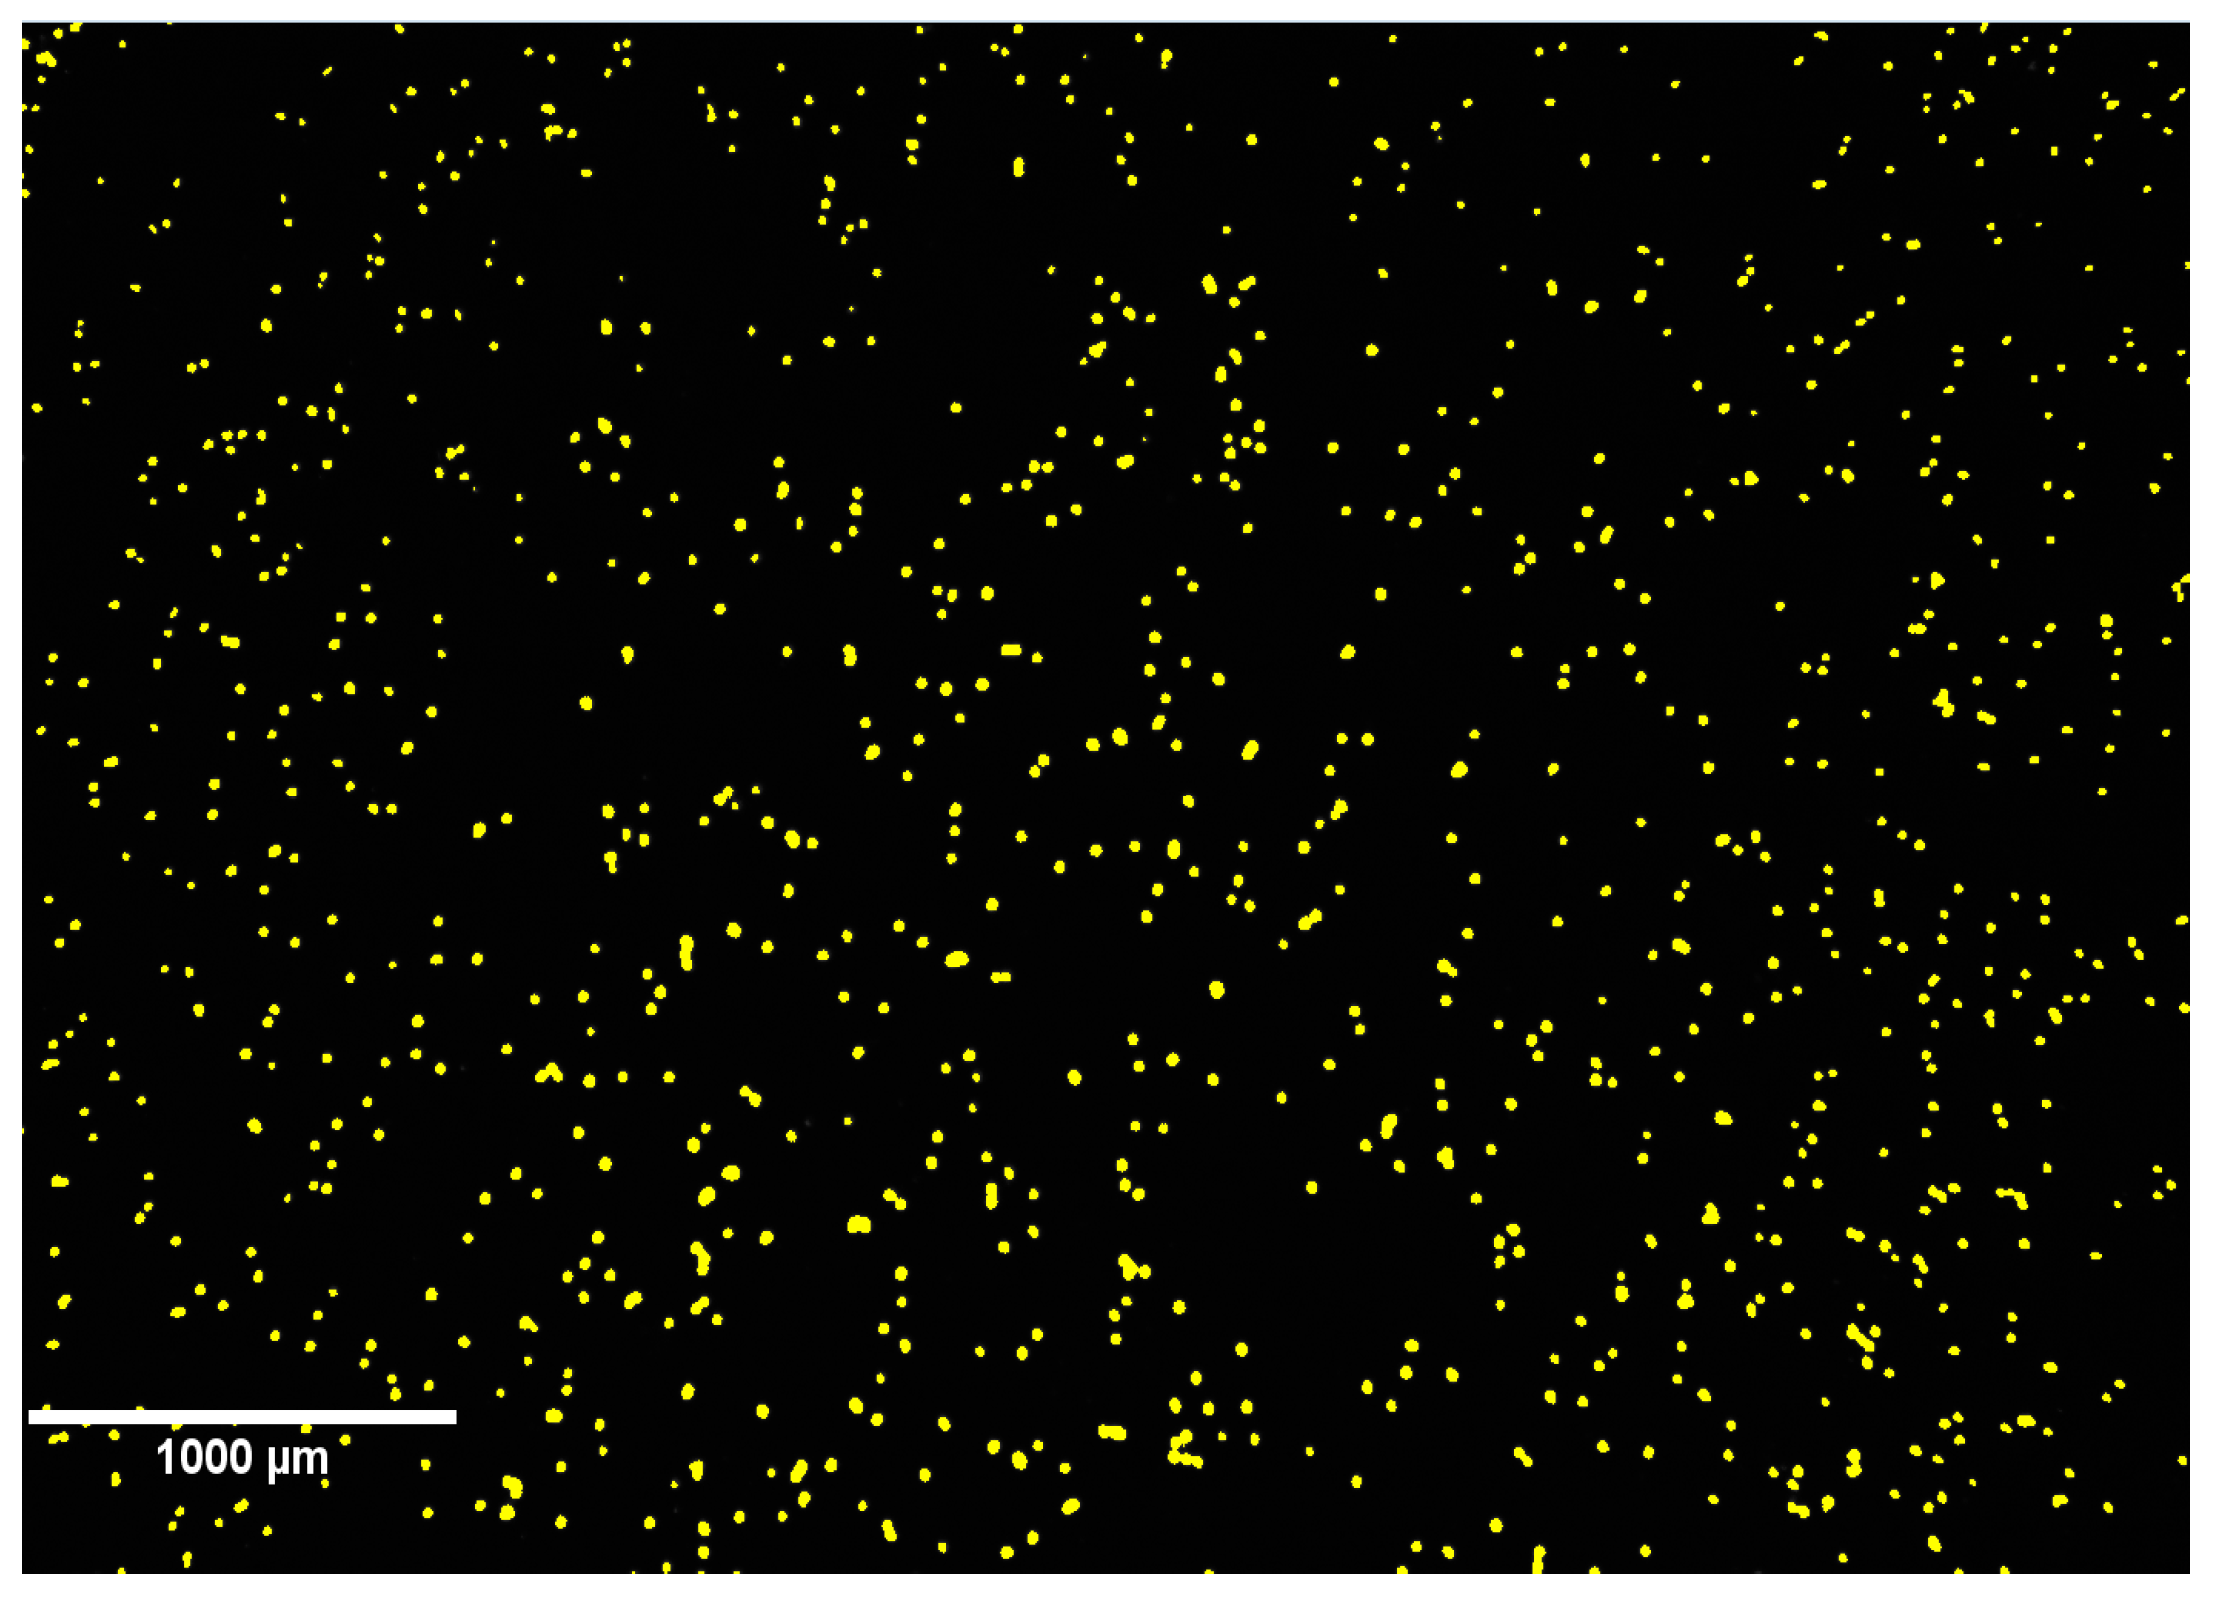

In order to use CIC for ex vivo quantification of the number of hepatocytes, we used a transgenic line Tg(fabp10a:DsRed) expressing DsRed in hepatocytes under the fabp10a promoter. To dissociate and recover hepatocytes from the larvae we investigated the effect of different common proteases (trypsin, collagenase and dispase) and mechanical forces (shaking, pipetting, and needle/syringe). We found that dispase, in combination with a gentle up and down pipetting of the digested larvae, resulted in a high recovery of well-separated and viable hepatocytes (Figure 5), whereas the other enzymes were not effective (collagenase) or highly toxic (trypsin) to the dissociated cells (results not shown).

Fluorescent hepatocytes present in the wells were imaged and counted on an IN Cell Analyzer 2000 using software IN Cell Investigator Developer Toolbox (GE Healthcare, Machelen, Belgium), with a 2×/0.1 NA lens, DsRed fluorescence channel, a 0.1-s exposure time, and the intensity segmentation (172-4095) set to ensure hepatocytes were recognized selectively.

Figure 5. DsRed-labeled hepatocytes captured by cell imaging counting (CIC). Yellow dots represent single hepatocytes.